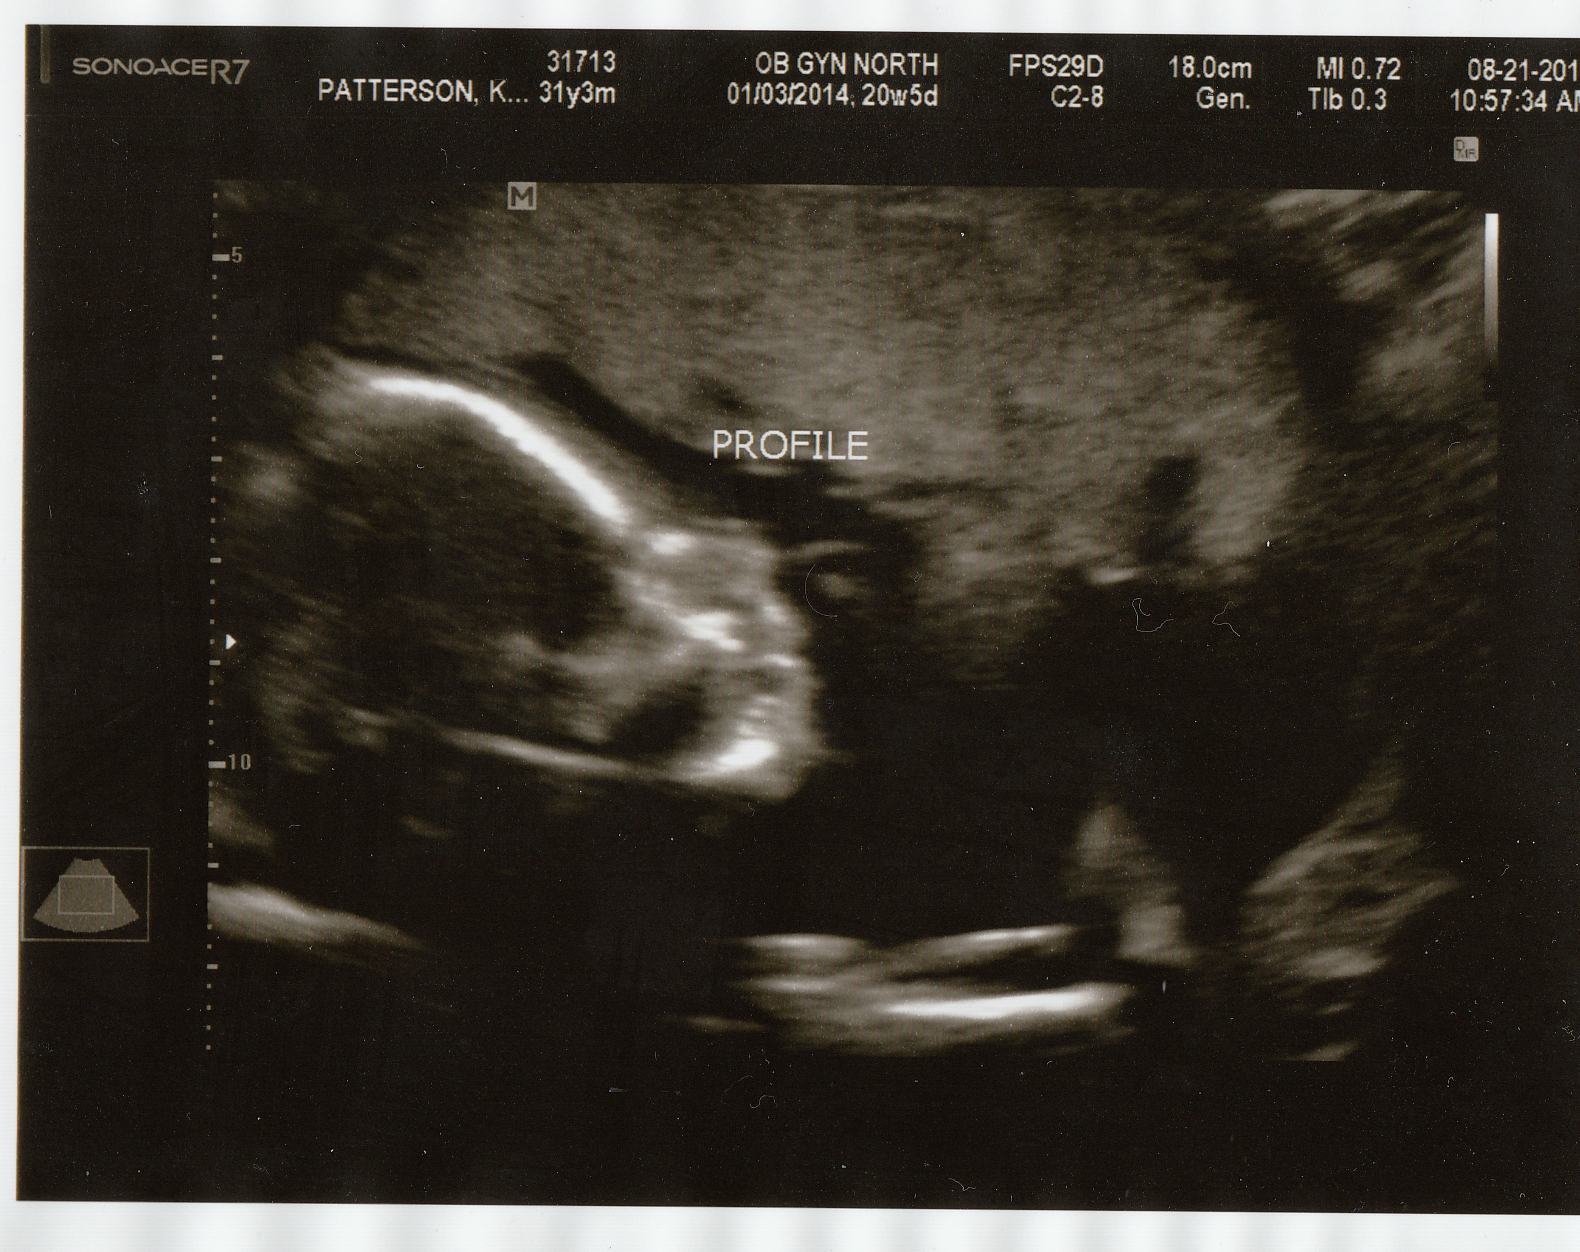

08.21.13 -4.5 months